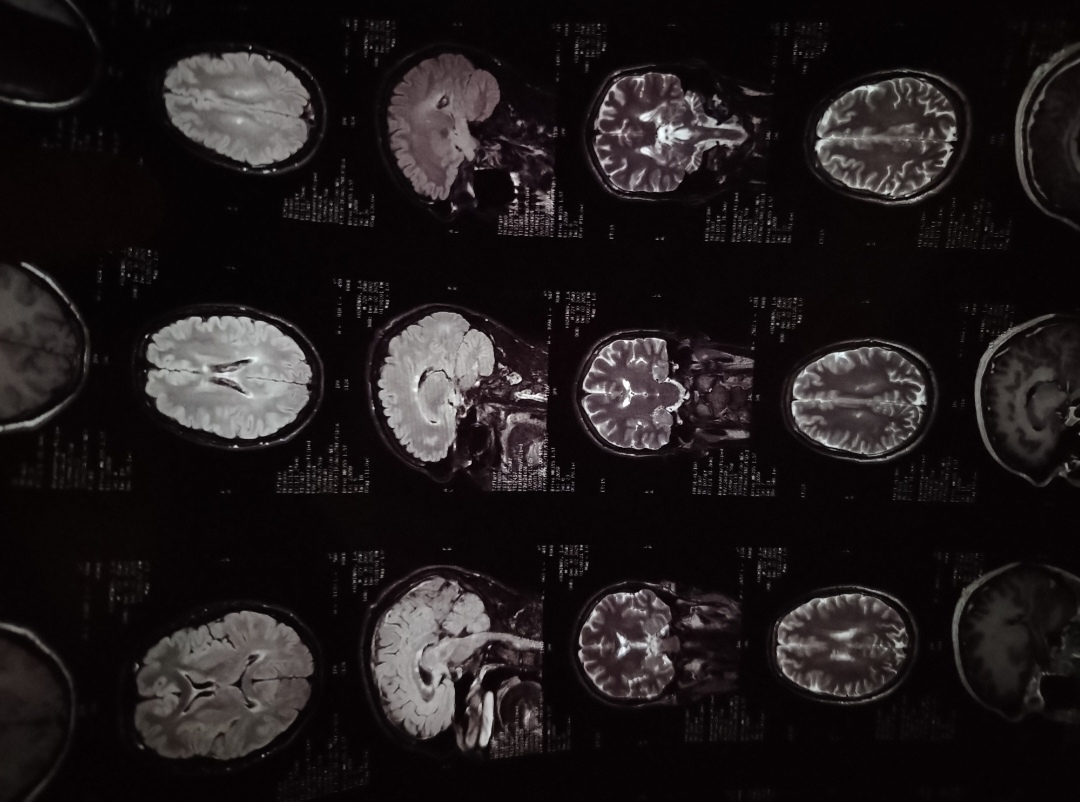

>>1644533 (OP)

На доске есть анонимы с рассеянным склерозом (РС, G35)?

Или я тут один такой "счастливчик"?

>>1630665 →-постер.

Аноним 19/10/25 Вск 08:05:49 1645488 18

>>1645262

Да нет, я сразу во время выполнения упражнения дискомфорт почувствовал, это всё из-за него. Года полтора назад я бы еще подумал, а теперь причина мне ясна. От турничка кстати у меня никогда проблем не было, да им и спину не так-то просто нагрузить